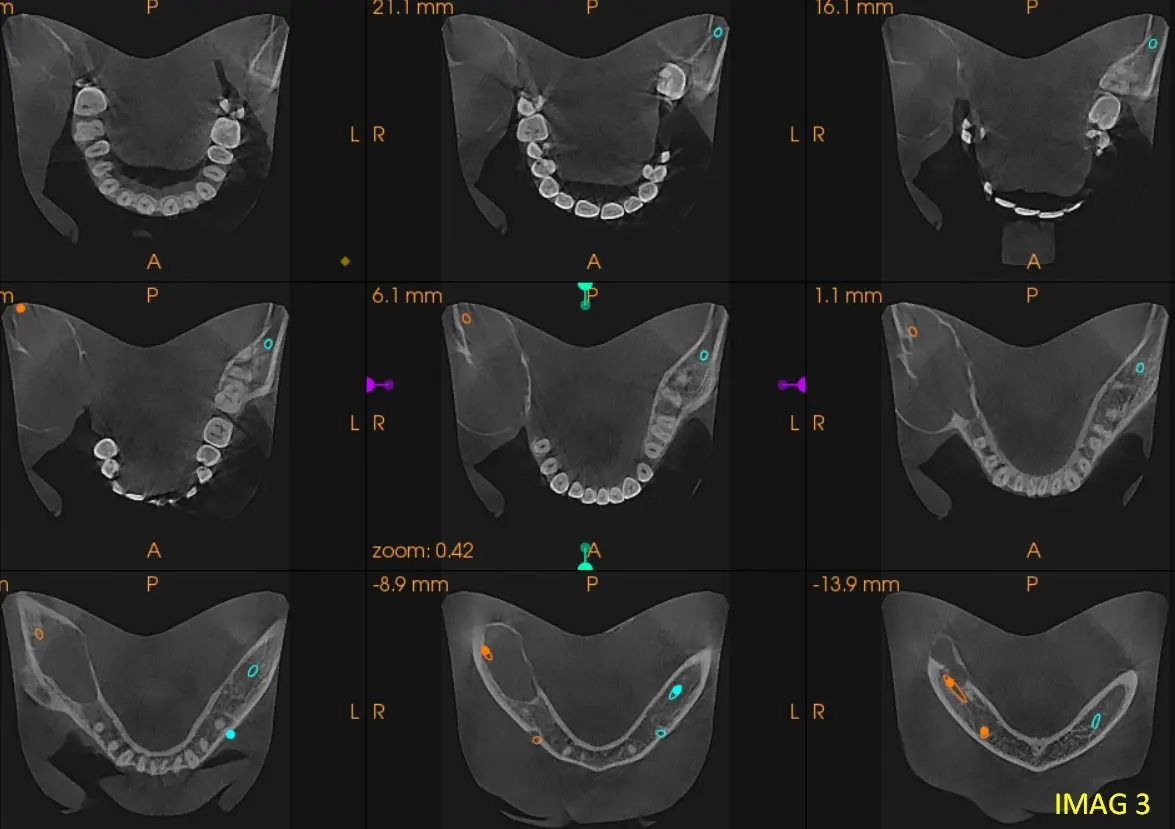

En los cortes sagitales y axiales de CBCT (ver imagen 2 y 3) se evidencia un marcado desplazamiento del conducto dentario inferior hacia el borde basal, acompañado de adelgazamiento y perforación de la cortical ósea, visible en la reconstrucción multiplanar (ver imagen 4). El contenido de la lesión es homogéneo, no se identifican tabiques internos ni calcificaciones que sugieran una lesión fibro-ósea, y la expansión y perforación cortical indican un comportamiento localmente agresivo. Por la combinación de las características: lesión unilocular, sin relación dentaria, desplazamiento del conducto y perforación cortical— el diagnóstico más probable es un ameloblastoma unicístico, considerando como segundo diagnóstico diferencial un queratoquiste odontogénico.